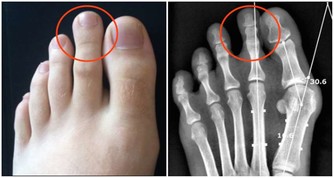

7、 腳痛

腳痛的時候,首先考慮為外傷造成,比如撞擊、擠壓、牽拉以及踩踏等,對於這種情況需要及時進行CT檢查,以免發生骨折。另外,當長時間走路,導致皮膚摩擦破損或者患有痛風的時候,也會引起疼痛。